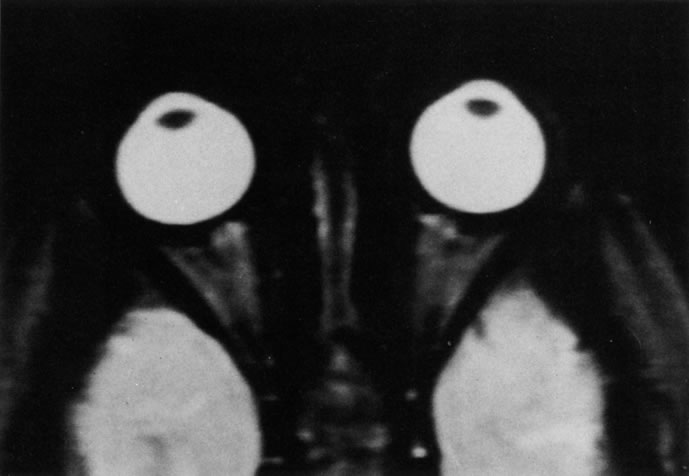

PATIENT PREPARATION Before MRI is performed, patients must be screened and prepared to avoid the potential hazards associated with the strong magnetic field. Patients who have ferrous aneurysm clips or cardiac pacemakers, who depend on life-support equipment, or who retain a possible metallic intraocular foreign body are not candidates for this imaging modality. MRI cannot be performed on obese patients who cannot fit into the bore of the magnet. Patients who are claustrophobic may not tolerate a prolonged period of study within the confines of the magnet, whereas others might do well if given a mild sedative. All worn metallic objects (e.g., necklaces, watches) should be taken off, credit cards set aside, and eye makeup removed before entering the room containing the magnet.5,20,34,35,36 NORMAL ORBITAL ANATOMY T1-weighted images provide the best anatomic details of the orbit because they display superior contrast resolution between normal structures (see Fig. 8). The vitreous has a long T1, resulting in an intermediate signal similar to brain, whereas the crystalline lens and sclera appear dark because of a longer T1 and short T2. The extraocular muscles, like all skeletal muscles, demonstrate a moderately long T1 and short T2 and highly contrast with the intense signal of the surrounding orbital fat (adipose tissue has an extremely short T1). The lacrimal glands appear as mottled areas of reduced intensity of the signal from the orbital fat in the lacrimal fossa. The optic nerves are seen with the same signal intensity as brain white matter and are hypointense relative to the orbital fat because their Tl is longer than the Tl of fat but shorter than the Tl of water. Cortical bone is not well delineated because it contains little free water, yielding minimal signal in MRI, and thus appears dark on all pulse sequences. This feature explains why MR images of the orbital apex and intracanalicular portion of the optic nerves are superior to comparable CT scans. Partial volume averaging of the bones in these regions obscures soft tissue details on CT images, whereas MRI reveals the signals only from the soft tissue structures with no cortical bone input. Bone marrow, on the other hand, is seen as a relatively intense signal because of its high fat content (see Fig. 8).37,38 T2-weighted pulse sequences are not ideal for imaging normal anatomy; however, they are particularly useful in revealing pathologic conditions (see Fig. 9). T2-weighted studies are most easily recognized by a bright vitreous signal. ORBITAL DISEASES Vascular Lesions Cavernous hemangiomas appear as well-circumscribed, smooth, usually intraconal masses that are isointense to muscle on T1-weighted images and hyperintense on T2-weighted images (Fig. 12). Patchy early enhancement is typically followed by diffuse, more homogeneous enhancement.39 The internal architecture of the mass, including septation and internal vasculature, may often be appreciated with high-quality orbital imaging.40 Lymphangiomas consist of ectatic vascular channels within a connective tissue stoma with varying degrees of lymphoid cellularity. On MRI, these tumors are typically poorly circumscribed, multicompartmental, and heterogeneous, often showing cystic dilations with fluid levels (Fig. 13). The signal characteristics within lymphangiomas vary considerably, reflecting cystic and solid components and the varying paramagnetic characteristics of blood at different stages of degradation.40–42 Acute hemorrhage appears hypointense on both T1- and T2-weighted formats. Methemoglobin present in subacute hemorrhage (3 to 14 days) leads to hyperintense signal on both T1- and T2-weighted images.41 A small percentage of lymphangiomas appear radiologically indistinct from orbital cavernous hemangiomas.43 Orbital varices are venous malformations that expand with increased systemic venous pressure, such as with Valsalva maneuvers. Because rapid acquisition of images during a Valsalva maneuver is important in imaging such a lesion, conventional or spiral CT is currently the modality of choice.44 MRI is an excellent modality for demonstrating enlargement of the cavernous sinus and dilation of the superior ophthalmic vein in patients with high-flow carotid-cavernous fistulas (Fig. 14).37MRA may be helpful in the evaluation of the venous outflow pattern. The rapidly flowing blood in these vascular structures carries the excited protons out of the section before they can be imaged, resulting in their dark appearance.5 In low-flow dural arteriovenous malformations, MRA may help define the arterial feeding vessels.45 Neural Lesions MRI is more effective than CT in delineating the intracranial optic nerves, chiasm, and optic tracts and, for this reason, is the preferred imaging modality in the evaluation of optic nerve disorders. The spatial relationships and image contrast of the orbital tissues with intraorbital optic nerve tumors is comparable between the two imaging modalities. The normal nerve is isointense to brain and appears enlarged and kinked owing to infiltration of an optic nerve glioma on T1-weighted images. Gliomas appear hyperintense on T2-weighted images and may be heterogeneous owing to cystic areas within the tumor. Contrast enhancement is variable.46 Intraorbital and intracranial optic nerve sheath meningiomas are usually isointense to cortical gray matter on Tl-weighted images and remain isointense on proton density studies (Fig. 15). Gd-DTPA is useful in delineating the intracranial extension of optic nerve meningiomas.7,47 The hyperostosis of bone and calcification associated with meningiomas are not demonstrated as well on MRI studies as on CT scans.20,37 Gd-DTPA–enhanced MRI also appears promising in the study of the permeability of the blood–brain barrier in selected optic neuropathies.22,48 MRI may reveal an enlarged optic nerve and some degree of contrast enhancement in cases of optic neuritis.49 Muscle Disorders Extraocular muscle enlargement in patients with thyroid-associated orbitopathy is demonstrated equally well with CT and MRI studies. However, the superior tissue contrast on MR images reveals better details of the relationships of the optic nerve to the thickened muscles at the orbital apex (Fig. 16).50 In addition, MRI may be able to differentiate between muscles that are enlarged as a result of edema and active inflammation and those enlarged because of fibrosis by their T2 relaxation times.21 Quantitative MRI was not found to be accurate in predicting the success of low-dose orbital irradiation.51 However, a muscular index relating the diameters of the rectus muscles to the bony orbital dimensions was useful in predicting optic nerve compression.52 MRI is also effective in imaging orbital tumors of mesenchymal origin, such as rhabdomyosarcoma, particularly in the assessment of extension into the anterior and middle cranial fossae (Fig. 17).37 The lack of any pathognomonic radiologic features necessitates rapid orbital biopsy when rhabdomyosarcoma is suspected. Osseous Lesions In general, CT is the imaging modality of choice when details of quantity and quality of bone are needed; however, abnormalities of bones can be detected indirectly by MRI. Cortical bone appears black (signal void) on MR images because of its low proton density and free-water content. The absence or discontinuity of the signal void of the orbital walls may represent bony destruction or fracture. Hyperostosis associated with prostate metastases or meningioma is visualized as areas of black smudging.50,53 Diseases in which the bone is replaced by pathologic tissues with a high free-water content, such as fibrous dysplasia, are well demonstrated on MRI. An intermediate signal intensity on T1-weighted images and hypointense signal on T2-weighted images is representative of fibrous dysplasia. Enhancement on post–Gd-DTPA MR scans is seen and is more evident in areas that are less mineralized.54 Cystic Lesions Dermoid cysts appear as rounded, well-defined lesions typically contiguous with an orbital bony suture. The high-intensity signal on T1-weighted images is attributed to the sebaceous-produced lipid contents (Fig. 18).31,50 Mucoceles may demonstrate a hypointense or hyperintense signal on MR images, depending on the concentration of proteinaceous or inflammatory fluid components. The integrity of the bony walls of the expanded sinus cavities cannot be assessed on MR as well as by CT.37,50,55,56 A high-signal intensity on Tl- and T2-weighted images is characteristic of orbital chronic hematic cysts because of the blood-breakdown products within the cysts.57 Trauma Although soft tissue relationships are usually better demonstrated on MRI, the evaluation of craniofacial bony trauma is preferable with CT. For example, prolapse of orbital fat through a fracture site and hemorrhage of adjacent tissues are demonstrated in an MR image, but the actual fractured bone is not imaged. Three-dimensional MRI of the orbit in subacute trauma has been described,58 although its precise role is not currently established. MRI has been suggested to be superior to CT in detecting intraorbital wooden foreign bodies.59,60 In a series of penetrating orbital injuries with organic foreign bodies, however, MRI was able to identify the foreign body in only four of seven cases.61 With an in vitro model for wood foreign body, McGuckin and colleagues concluded that CT was the imaging modality of choice.62 A careful history and, in selected cases, plain films to rule out a metallic foreign body are crucial before MRI is considered in patients with periocular trauma. MRI is particularly helpful in the detection and characterization of subperiosteal hematomas of the orbit (Fig. 19). They are most commonly seen in the subperiosteal space of the superior orbit as well-defined masses following a traumatic injury. The signal intensity varies depending on the acute, subacute, or chronic nature of the hematoma, based on the stage of blood degradation. Fresh hemorrhages are hypointense on T1-weighted images and hyperintense on T2 images. Hematomas that are 1 to 7 days old are hypointense on both T1- and T2-weighted images. T1-weighted images of hematomas more than a week old are hyperintense due to the oxidation of deoxyhemoglobin to methemoglobin, whereas the T2 images remain hypointense.63 Metastatic Tumors Breast carcinoma metastatic to the orbit has been demonstrated to be hypointense to the surrounding orbital fat on T1-weighted studies and hyperintense on T2-weighted images and has an affinity to the extraocular muscles (Fig. 20).50,64 The MRI characteristics of prostate carcinoma metastatic to the orbit have been described as involving the greater and lesser wing of the sphenoid, orbital roof, and optic canal. Diffuse bone hypertrophy with isointense or slightly hyperintense tissue on T1-weighted images represents the osteoblastic carcinomatous bone infiltration. Contrast enhancement is variable on T1-weighted and fat-suppressed images.65 Most other metastatic tumors also have a lower intensity signal on T1-weighted images and appear to displace or infiltrate normal orbital structures; however, their signal characteristics are variable on T2-weighted MR images.66 Many metastatic tumors demonstrate bright contrast enhancement with Gd-DTPA. Infectious Disorders MRI findings of preseptal and orbital cellulitis typically include increased signal intensities on T2-weighted images of the eyelids and orbital fat, respectively, due to the increased water content of the tissues. Since most cases of bacterial orbital cellulitis are associated with paranasal sinusitis, hyperintense signals of the affected sinuses may also be found on T2-weighted images as well as enhancement of polyps and granulation tissue on postgadolinium T1-weighted MR images. Subperiosteal abscess formation may occur due to contiguous spread of infection from the paranasal sinuses and appear on MRI as an area of intermediate signal on T1-weighted and proton-weighted MR images. The abscess may appear slightly hyperintense compared with muscle on T2-weighted scans with the necrotic contents having the greatest intensity.67 MRI and MRV are more sensitive than CT in revealing cavernous sinus thrombosis. Engorgement of the cavernous sinus, extraocular muscles, and ophthalmic veins is seen with hyperintensity of the thrombosed sinuses evident on all pulse sequences. The enlarged, thrombosed superior ophthalmic vein appears less hypointense than the normal contralateral ophthalmic vein, and hyperintensity within the lumen of the vessel may be seen on T1- and T2-weighted MR images.68 Inflammatory and Lymphoproliferative Lesions Inflammatory conditions of the orbit, both idiopathic (inflammatory pseudotumor) and those of known causes, have been found to be hypointense to fat and isointense to muscle on Tl-weighted studies and isointense or slightly hyperintense to fat on T2-weighted images (Fig. 21).50,64,69 The more fibrous or sclerosing varieties have less signal intensity on T2-weighted images. Marked enhancement is seen in pseudotumor infiltrates after gadolinium administration.70 The same signal characteristics are demonstrated in patients with Tolosa-Hunt syndrome, with mass lesions seen in the cavernous sinuses and orbital apices.71 Lymphomas have MRI characteristics similar to those of inflammatory lesions in that they are hypointense to fat and isointense to muscle on T1-weighted images (Fig. 22). They may appear hyperintense to fat on T2-weighted images, perhaps owing to less fibrosis than that seen in orbital inflammatory pseudotumor, although this is not a consistent finding.31,50,66 Lymphoid tumors typically enhance moderately after contrast injection. Unfortunately, studies have shown that tumor density and homogeneity are similar between inflammatory and malignant orbital infiltrates, and MRI cannot differentiate these lesions.72,73 Lacrimal Gland Tumors Lacrimal gland lesions present special problems in diagnosis and management. Pleomorphic adenoma (benign mixed tumor) should not be biopsied, but rather excised in toto. On the other hand, for lymphoma and inflammatory infiltrates, incisional biopsy is more appropriate than complete excision of the lacrimal gland. Thus, preoperative clinical and radiologic evaluation are especially crucial in planning appropriate surgical management. Pleomorphic adenomas demonstrate long T1 and T2 signal characteristics. They may show heterogeneity on T2-weighted images74 and moderate to marked enhancement with contrast.75 Signal characteristics of adenoid cystic carcinoma include hypointensity to fat on T1-weighted images, hyperintensity to fat with increased T2 weighting, and isointensity to fat on proton density-weighted studies (Fig. 23).31,75 Secondary bony alterations of the lacrimal fossa associated with lacrimal gland tumors, such as remodeling (benign mixed tumor) or destruction (adenoid cystic carcinoma), are seen indirectly on MR images; however, bone windows on CT scans provide better delineation of these changes. In contrast to the round or globular appearance of benign or malignant epithelial tumors of the lacrimal gland, lymphoproliferative tumors usually appear to be molding or draping onto the globe and the surrounding bony orbit. LACRIMAL DRAINAGE SYSTEM DISORDERS MRI with surface coils provides excellent spatial resolution and tissue-specific signal intensities of the lacrimal drainage system. These parameters have been found useful to more accurately demonstrate the extent of lesions in the lacrimal sac and differentiate long-standing mucoceles from solid tumors than CT.76 Physiologic studies in patients with tearing disorders now include MR dacryocystography, in which Gd-DTPA is either placed topically in the conjunctival fornix or injected by cannulation into the lacrimal sac. They provide a detailed morphologic and functional analysis of the lacrimal excretory system; however, they are no more sensitive than digital-subtraction dacryocystography or CT dacryocystography.77–79 INTRAOCULAR TUMORS On MRI, uveal melanomas have a typical appearance that helps to differentiate them from other primary and secondary intraocular tumors as well as choroidal detachments. Pigmented melanomas are hyperintense on Tl-weighted images, hypointense on T2-weighted studies, and hyperintense on proton density–weighted examinations (Fig. 24).30,31,50,80–82 These signal characteristics have been attributed to the paramagnetic properties of melanin because of stable free radicals that shorten the T1 and T2 relaxation times. Moderate enhancement is seen on postgadolinium T2-weighted images. Gadolinium-enhanced T1-weighted images are particularly sensitive in detecting choroidal melanomas.83 MRI may be less sensitive in detecting extrascleral extension of tumor than echography performed by an experienced ultrasonographer.84 Tumors metastatic to the choroid are hyperintense on T1- and T2-weighted images.24 The signal characteristics, however, may be similar to those seen with choroidal melanoma. Choroidal hemangiomas, on the other hand, have an intermediate signal on T1-weighted sequences and become hyperintense on T2-weighted images50 as well as proton density–weighted images.81 Retinoblastomas display moderate signal intensity on T1-weighted studies and a low signal on T2-weighted images.31,80,85 Calcification can be easily detected by CT and ocular ultrasonography but is not imaged by MRI.25,50 The presence of optic nerve involvement is best evaluated by MRI. ACQUIRED ANOPHTHALMIA When an eye is removed owing to tumor or trauma, an implant is typically placed in the intraconal space. MRI may be useful in defining the size, shape, and position of such orbital implants.86 Porous hydroxyapatite or polyethylene implants are preferred by many surgeons performing enucleation or evisceration. A porous implant offers the possibility of supporting a motility coupling peg to increase the movement of the overlying prosthesis. MRI with contrast is used by some surgeons to evaluate the degree of fibrovascular ingrowth in hydroxyapatite87 and porous polyethylene88 implants prior to motility peg placement. |